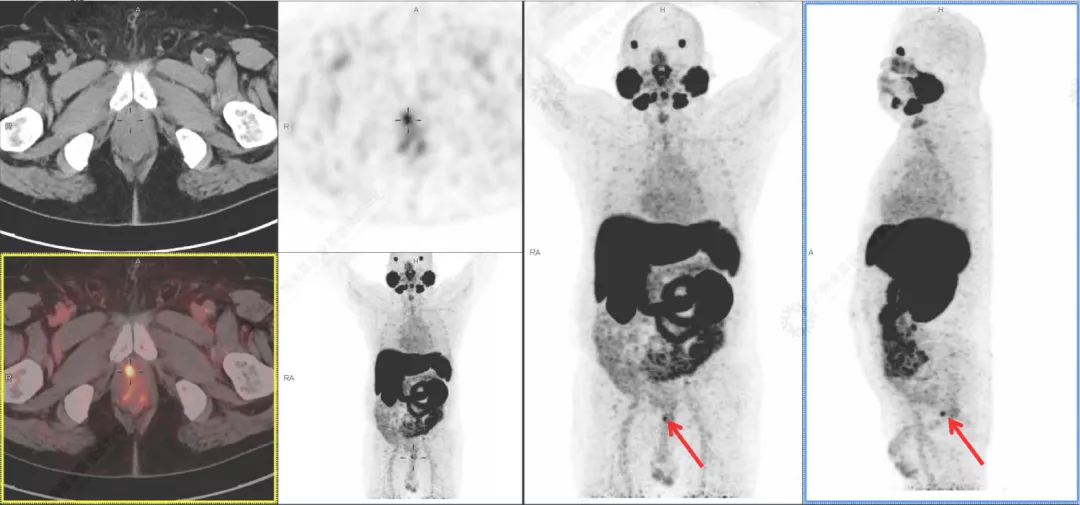

2. 《18F-PSMA靶向PET/MRI成像技术在前列腺癌中的应用价值》 汇报人曾玉萍

从MRI的优势及不足、PET/MR特点、前列腺特异性膜抗原等几个方向进行讲解,并例举案例辅助说明。

案例展示: